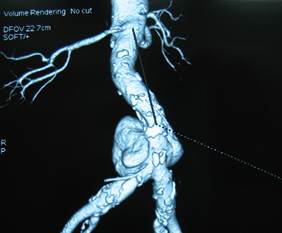

Thương tổn trên phim cắt lớp và/hoặc cộng hưởng từ

Hình dạng: Hình thoi: 7 bệnh nhân (26%). Hình túi: 20 bệnh nhân (74%).

Kích thước: Trung bình: 58.2 ± 21 mm.        Lớn nhất: 100 mm.   Nhỏ nhất: 20mm.

Hình 1: Phình động mạch chủ bụng hình túi trên CT Scanner